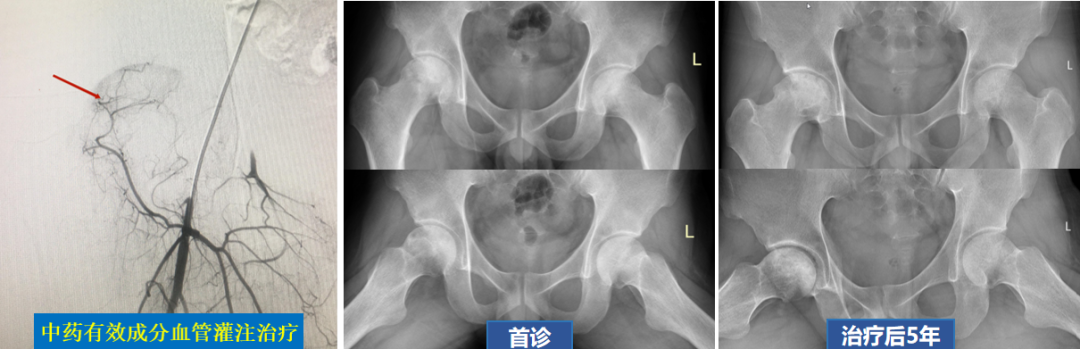

4.中药局部血管给药:将活血化瘀类中药靶向输送至股骨头的供血血管,以促使病变部位血管扩张,改善骨内微循环状态,促进代谢废物清除与血管再生。

1.非手术治疗

DSA造影显示左侧股骨头血运状态良好,经非手术综合保髋治疗后,坏死骨修复良好,股骨头形态稳定。